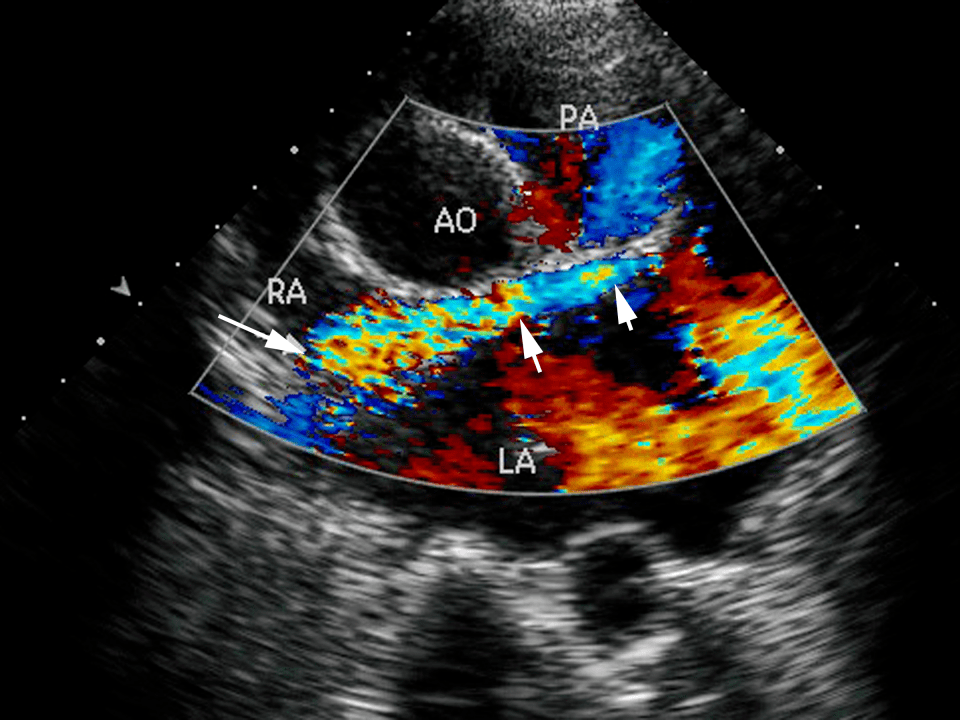

彩色多普勒血流显像图册